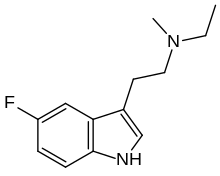

| 5-Fluoro-MET | artificial | 5-F | CH3 | CH2CH3 | 5-fluoro-N-methyl-N-ethyltryptamine | |